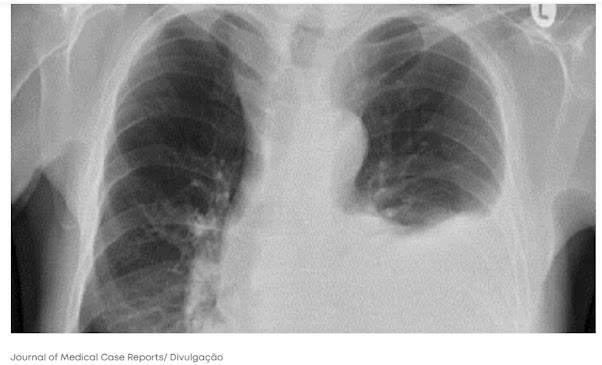

Radiografias de tórax revelaram um quadro de quilotórax, caracterizado pelo acúmulo de líquido leitoso entre as camadas que revestem os pulmões, chamadas de pleuras. Isso acontece quando o sistema linfático, responsável por drenar o excesso de fluidos do corpo, é interrompido.

Exames mais detalhados mostraram um tumor benigno comprimindo os pulmões. O caroço tinha 7 cm e pressionava o ducto torácico — um importante vaso linfático — impedindo que o fluido saísse do corpo.